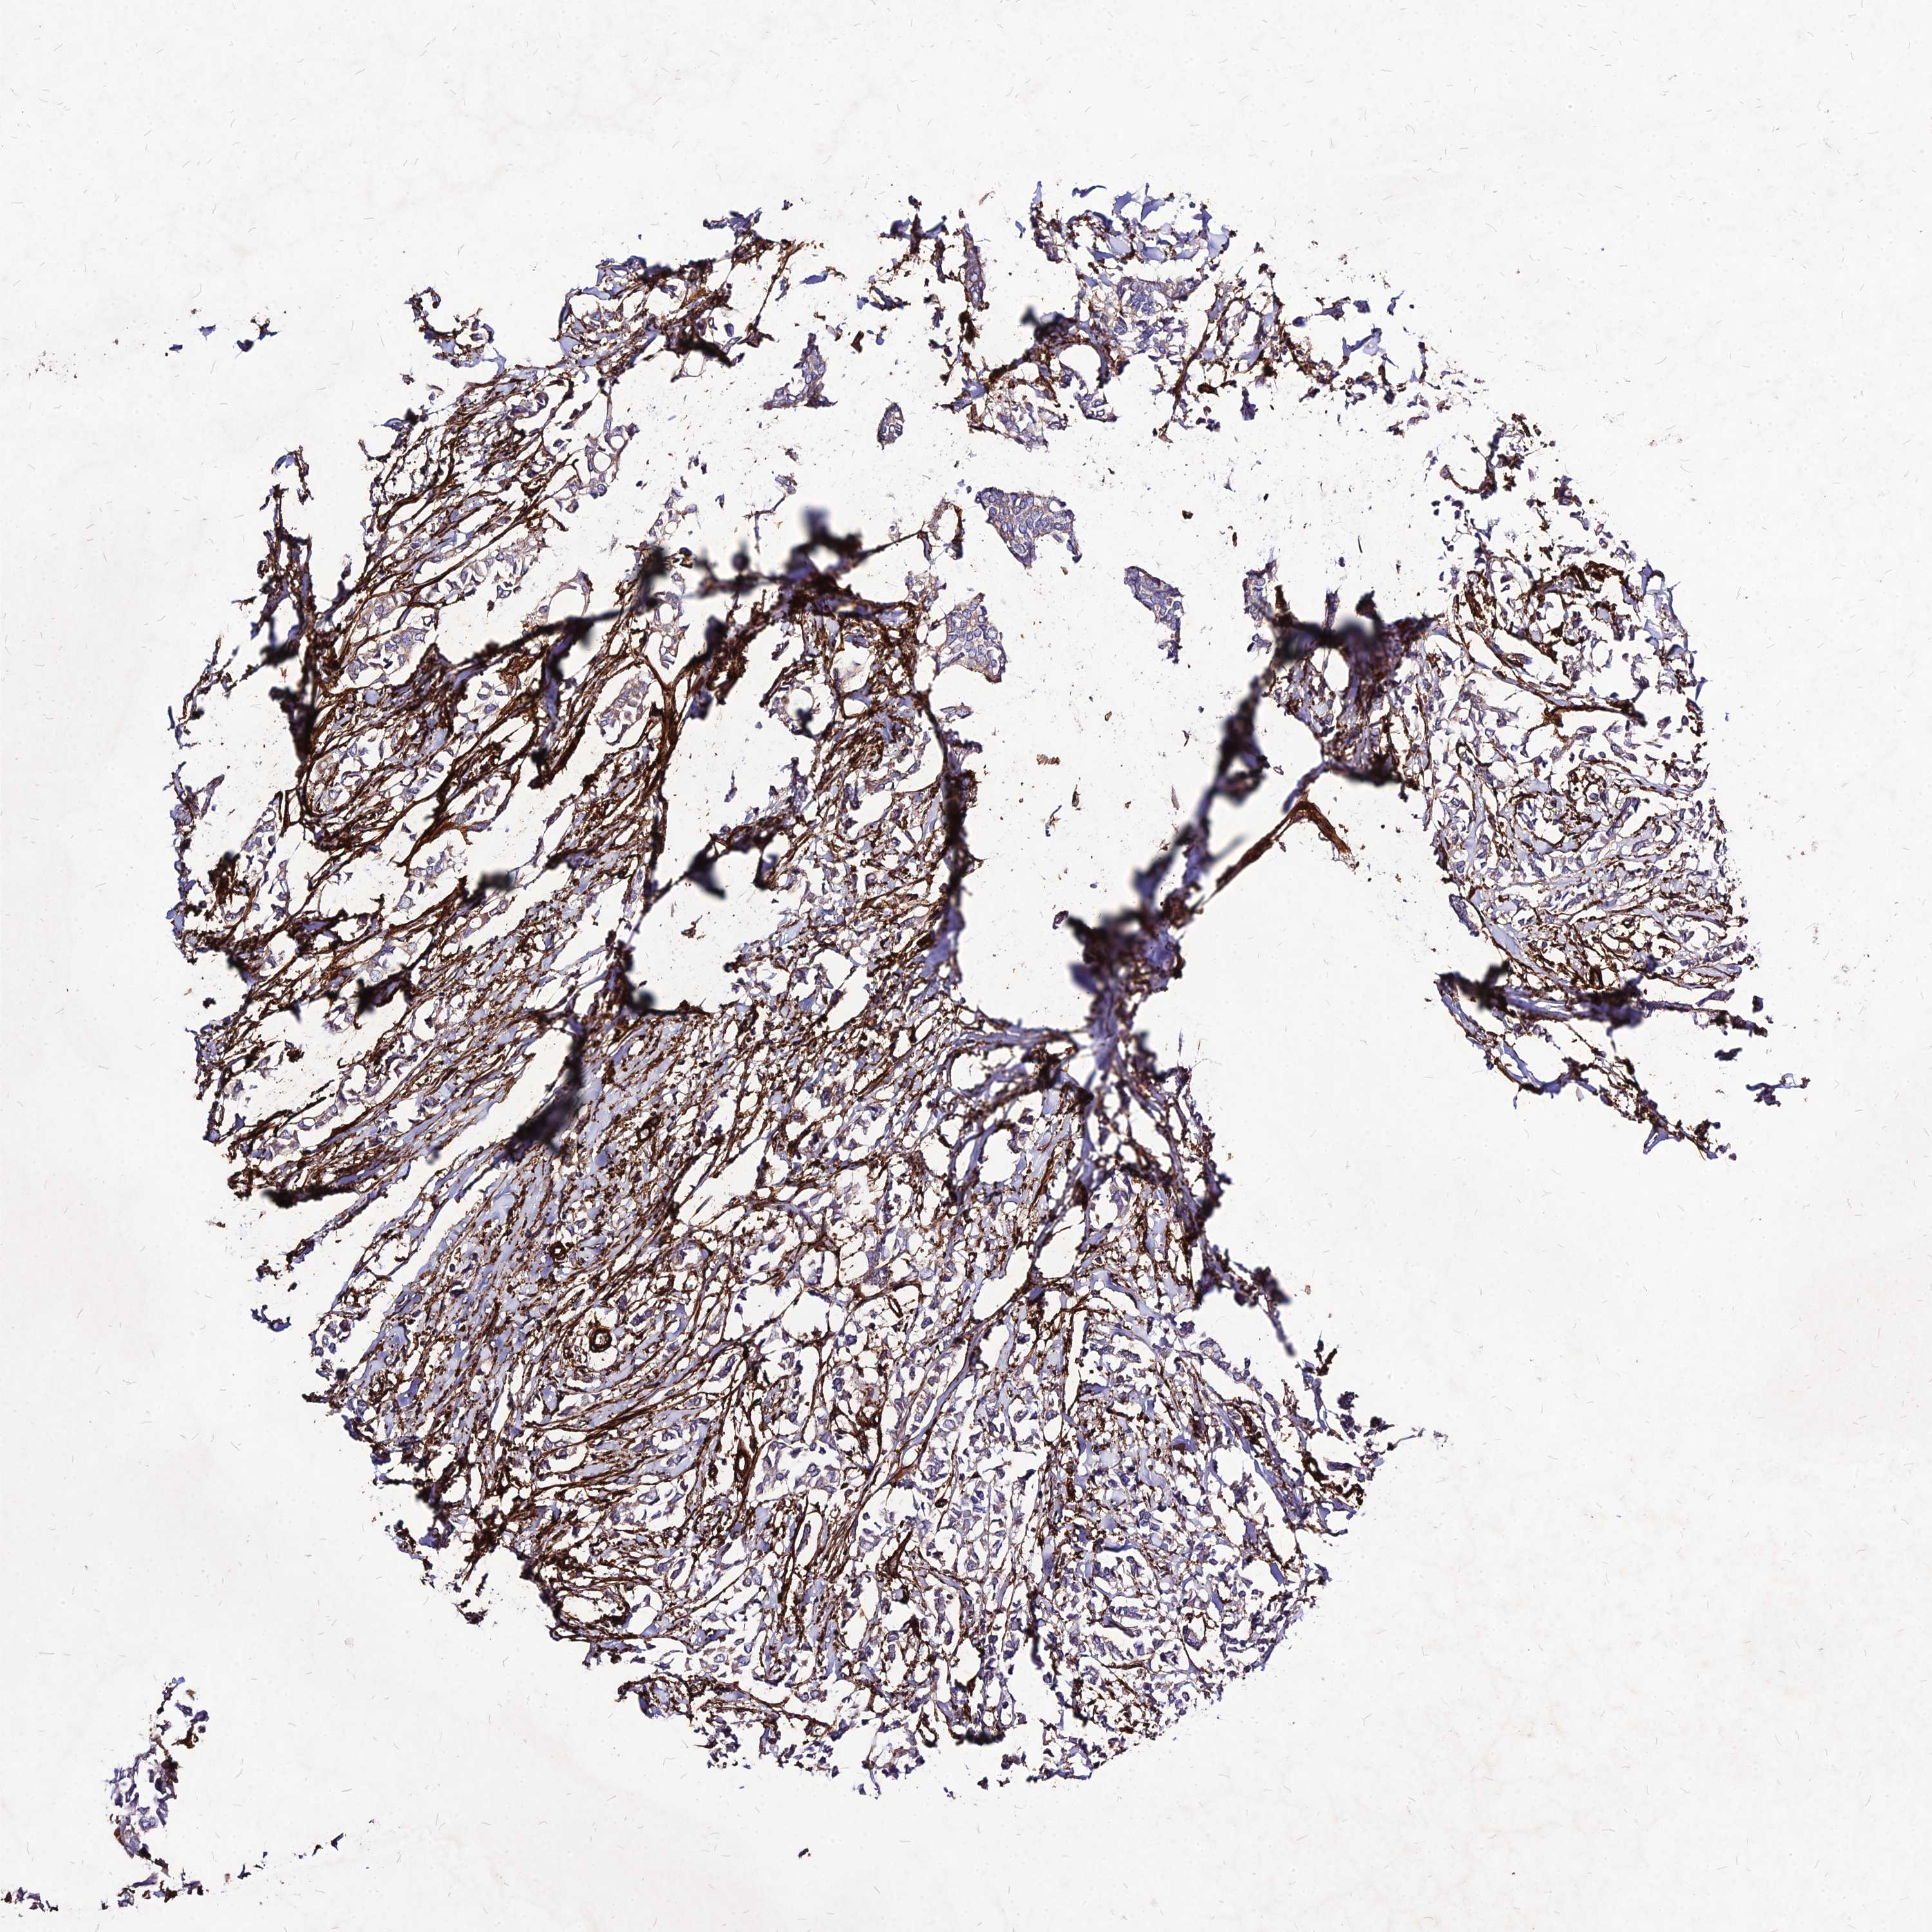

BRCA TCGA BRCA VALIDATION PROTEIN EXPRESSION

ANTIBODIES

AND

VALIDATION